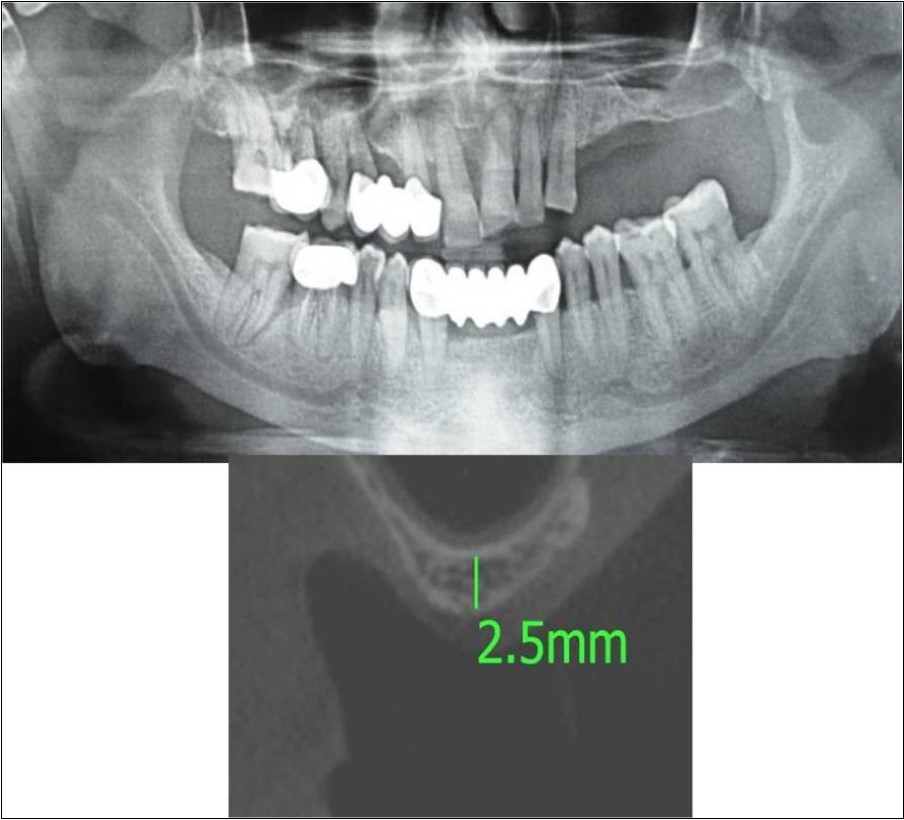

Clinical and Radiological Assessment:

3.Height of available bone- 2.5mm;

Treatment:

Patient underwent the procedure of direct sinus elevation using sinus lateral approach kit. After crestal and vertical release incisions, muco-periosteal flap was raised to expose the buttress region. A bony window of 1cm diameter was created; sinus lining identified and elevated up to receive calcium phosphosilicate as graft material and closure was achieved under local anaesthesia and strict aseptic protocols. Implant placement was planned to be carried-out after a period of 6 months to allow for the consolidation for graft and naive bone formation. At the end of 6 months, a repeat CBCT scan was advised to evaluate the increase in bone height. (Figure 15a,b, pre-treatment; Figure 16a,b, post-treatment)

Figure 15.a,b. Pre-treatment OPG and cross section of CBCT showing residual alveolar bone height for Case No.5;

Figure 16.a,b. Post-treatment OPG and cross section of CBCT showing residual alveolar bone height for Case No.5;